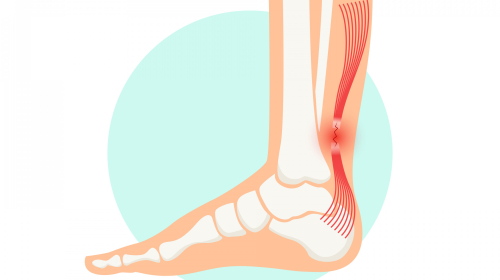

- Achilles ruptures

- Tendon disorders